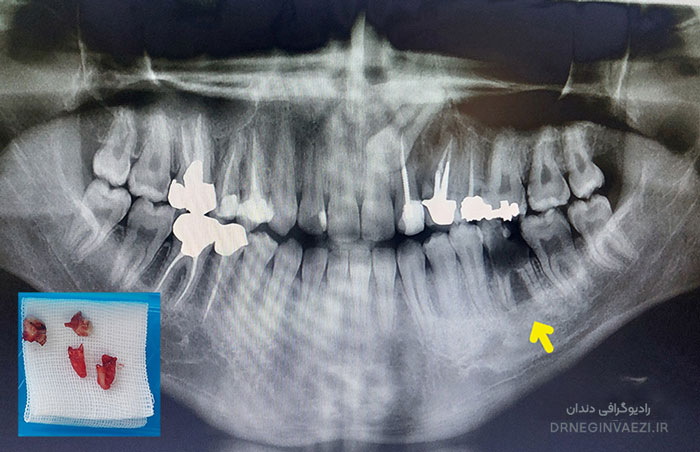

در این نمونه درمان انجام شده در مطب ولیعصر تبریز (جراحی و اکسترکشن)، معاینه و رادیوگرافی نشان داد که دندان دچار عفونت گسترده و تخریب ساختاری شده است.بدلیل غیر قابل نگهداری بودن دندان بعلت پوسیدگی و عفونت شدید  جراحی دندان تنها گزینه مناسب برای حفظ سلامت دهان و جلوگیری از عوارض بیشتر بود.درمان بعدی برای جبران دندان از دست رفته، بریج دندانی یا درمان بهتر ایمپلنت می تواند باشد. که البته درمان بعدی پس از رفع عفونت و تشکل استخوان در ناحیه قابل انجام خواهد بود.

تصویر قبل از جراحی دندان عفونی و تخریب‌ شده

تصویر رادیوگرافی دندان خراب و نکروز شده بیمار مطب دندانپزشکی دکتر نگین واعظی

گرافی دندان و تصویر دندان خارج شده